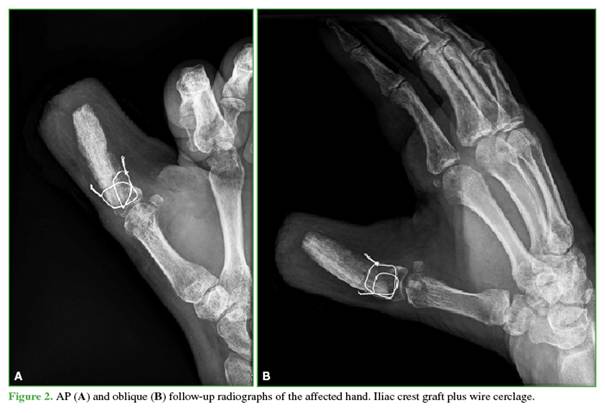

A 58-year-old male pharmacist presented with a traumatic amputation of the thumb at the metacarpophalangeal level, with a failed replantation attempt, in his dominant hand. Because he declined reconstruction using a toe-to-hand transfer, osteoplastic reconstruction was proposed (Figure 1).

3)                  Fixation of the iliac crest graft: the graft was stabilized to the remaining base of the proximal phalanx using wire cerclage in the coronal and sagittal planes of the metacarpophalangeal joint, supplemented with temporary Kirschner wires. If tendon remnants are present, a tenoplasty may be performed; this was not required in our patient (Figure 2).